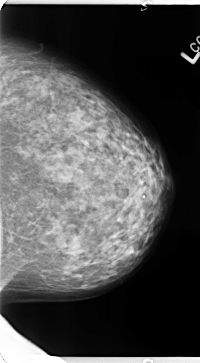

B_3133_1.LEFT_CC

LEFT_CC LINES 4712 PIXELS_PER_LINE 2600 BITS_PER_PIXEL 12 RESOLUTION 50 NON_OVERLAY